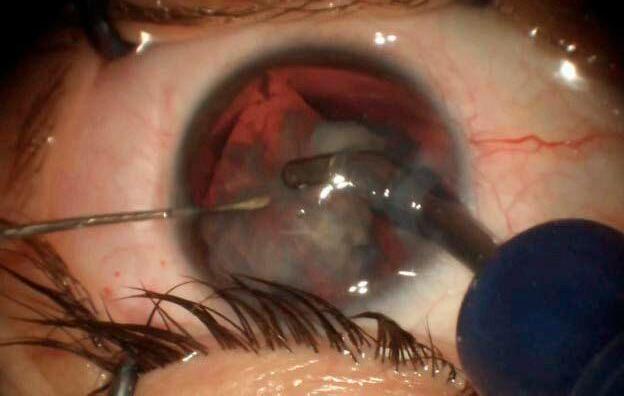

7.b Rotura capsular: del susto al rescate ordenado

Si bien hay una vasta recopilac ión de información y evidencias acerca de factores que pueden predisponer una ruptura capsular, como también de posibles soluciones intraquirúrgicas ante la aparición de la complicación, 46-48 creo que un interesante aporte es compartir experiencias: en una cirugía reciente, un paciente con alta miopía y cápsula muy elástica terminó con una dehiscencia posterior en la fase final del faco. La lente planificada era una EDOF tórica. Ante la situación, utilicé una técnica mixta: realicé una captura óptica con una lente de 3 piezas, utilizando los restos del borde anterior como soporte, y logré un centrado perfecto. Ese caso, como tantos otros, me recuerda que la tecnología es útil, pero la técnica salva cirugías.